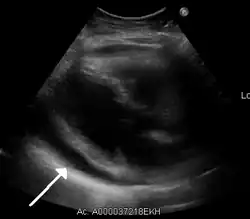

- echokardiografia – metoda z wyboru do rozpoznania (wykrywa nawet niewielką ilość płynu, u osób z tak zwanym suchym zapaleniem osierdzia jest nieskuteczna) i monitorowania leczenia